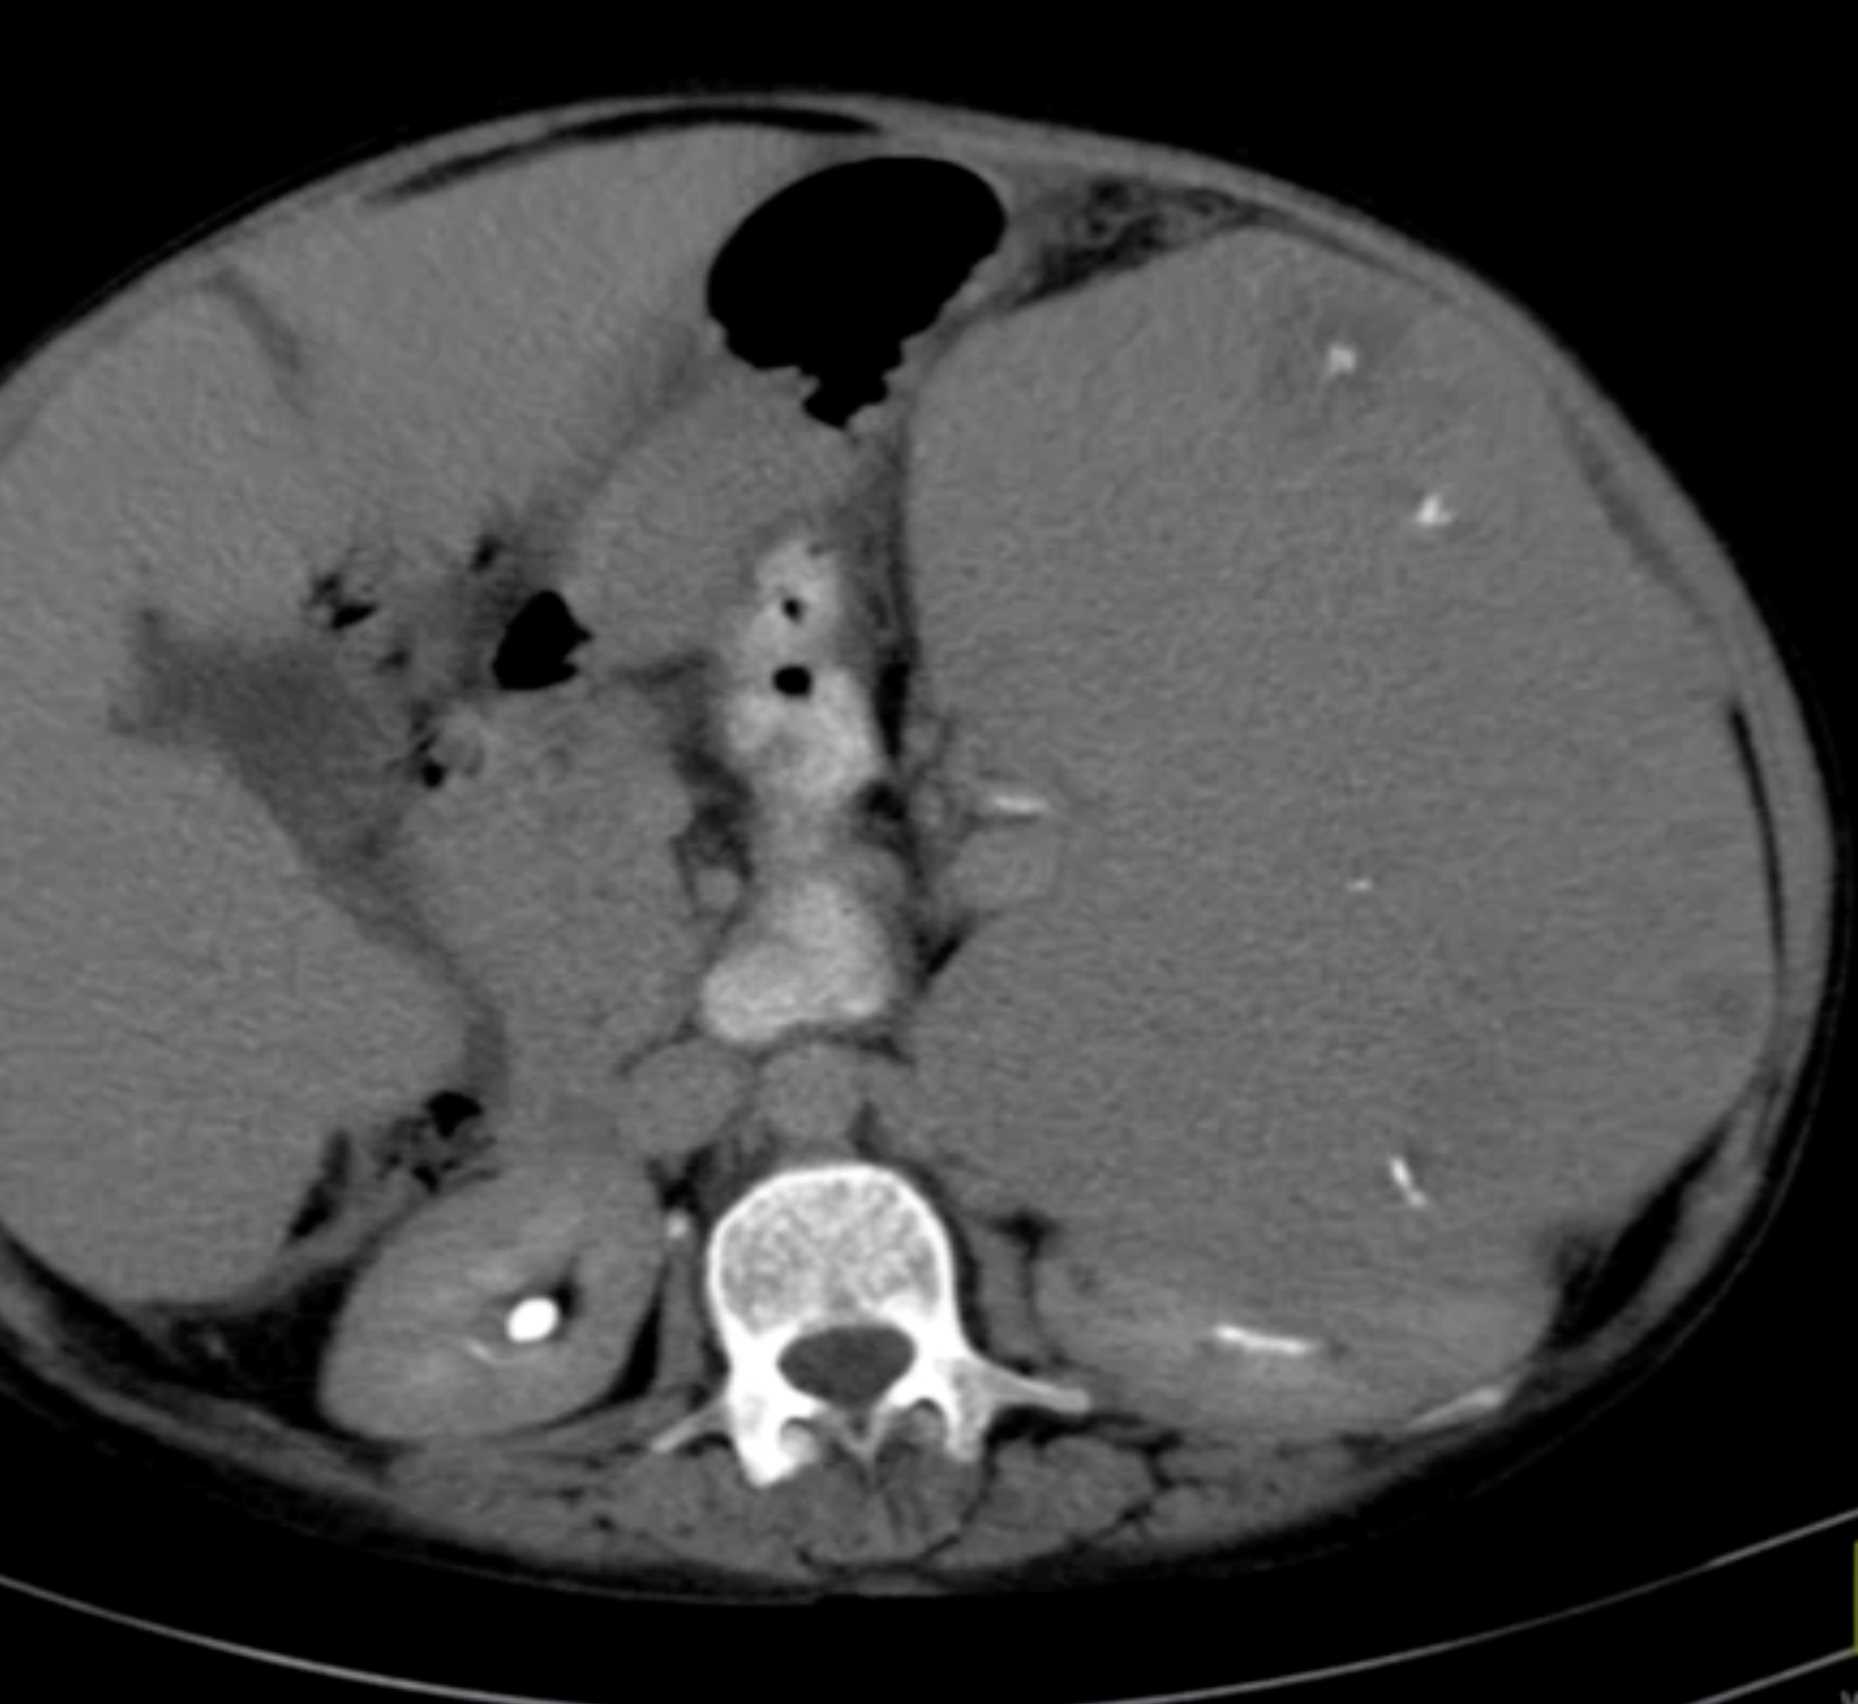

Gaucher's Spleen